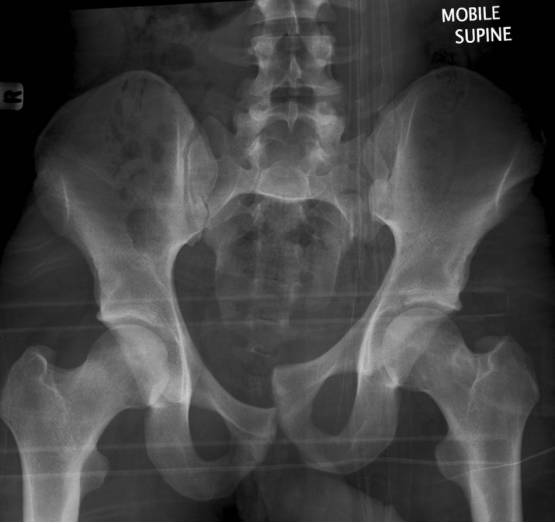

Malgaigne骨折

指垂直不稳定骨盆骨折,骨折累及双侧耻骨支、骶髂关节或者骶骨。

Duverney骨折

直接暴力导致的髂骨翼单独骨折,没有骨盆环的分离移位。